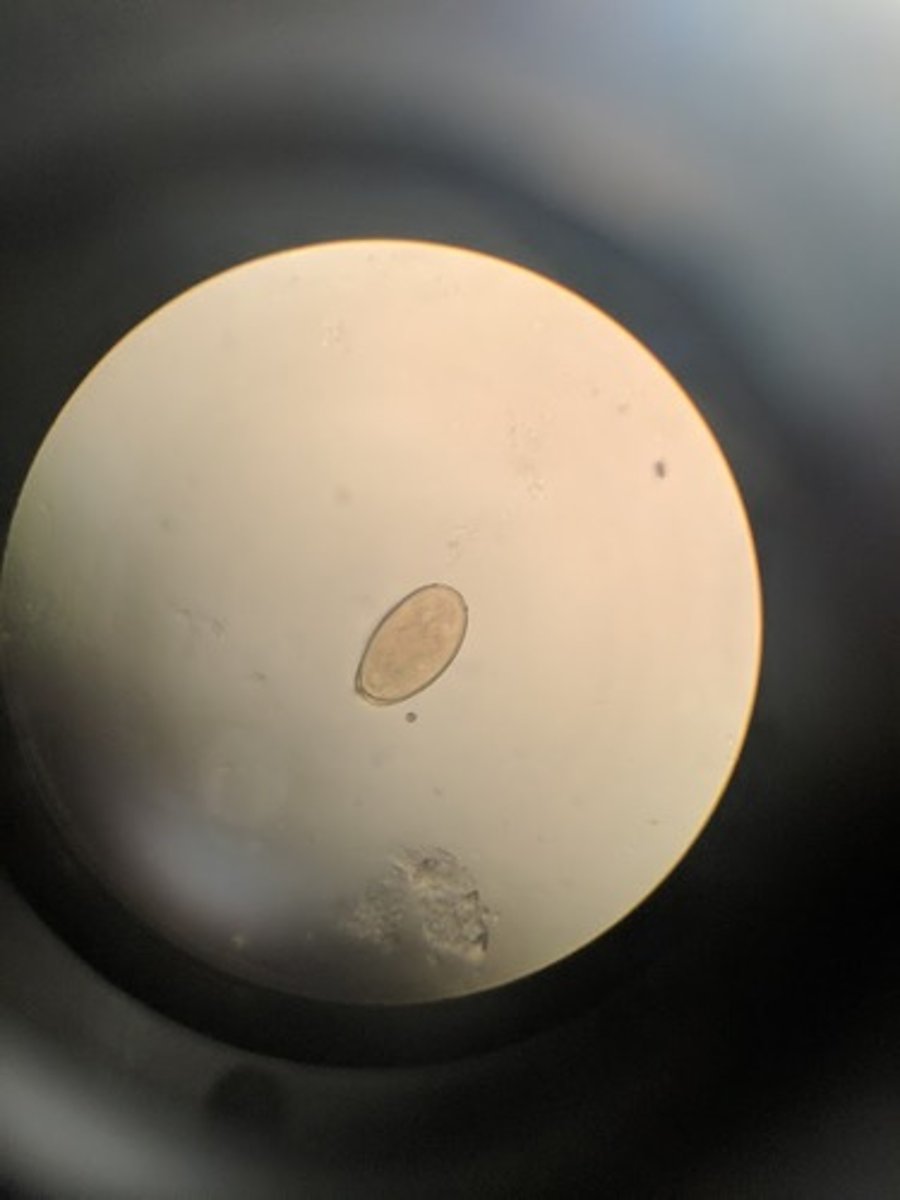

Giardia lamblia cyst

Ingestion of cysts in contaminated drinking water

- Oval with well defined cyst wall

- four nuclei present at one pole